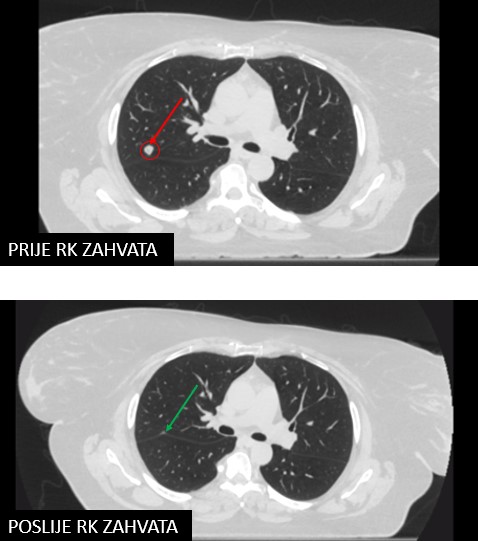

Rezultat – 40 mjeseci nakon RK

Potpuni nestanak tretirane lezije

Potpuni nestanak tretiranih lezija